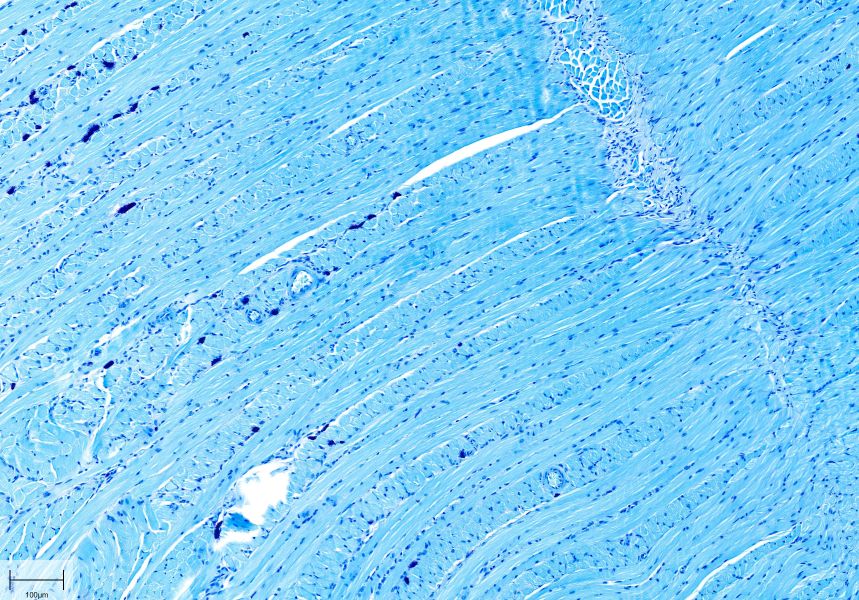

LFB染色